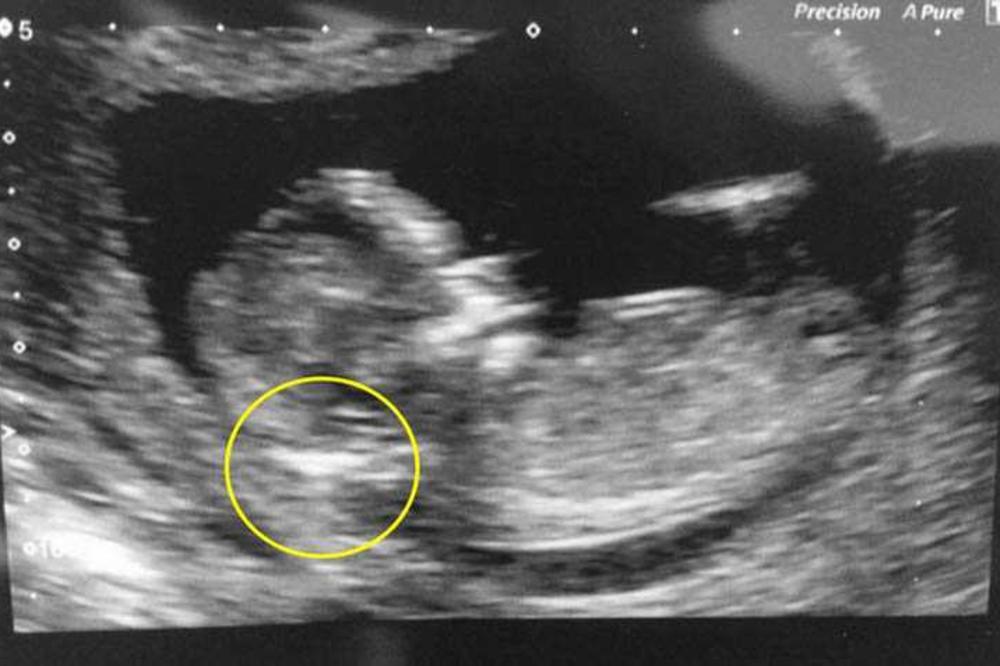

Britanka Džordan Skvajers (22) doživela je potpuni šok u 12. nedelji trudnoće kada joj je ginekolog nakon urađenog ultrazvuka pokazao detalj na bebi koji, kako joj je objasnio, ukazuje na to da beba zasigurno ima Daunov sindrom i posavetovao joj da "što pre okonča trudnoću".

Ginekolog mi je rekao da što pre abortiram. Uopšte mi nije dao bilo kakvu drugu opciju, samo je prokomentarisao da "zakažem abortus što pre". Kako mi je objasnio, budući da beba ima veliku količinu tečnosti u potiljku, sigurno će se roditi sa Daunovim sindromom - prepričava majka.